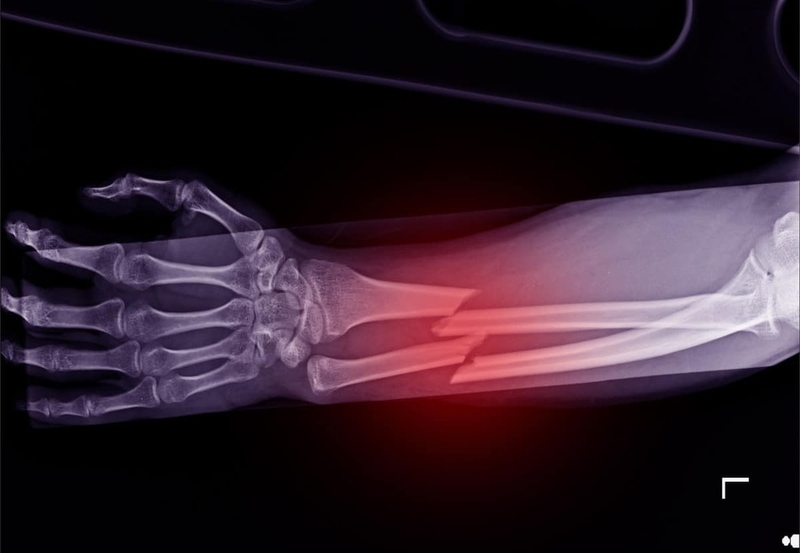

Theo đó, có nhiều cách gãy xương khác nhau. Hầu hết các trường hợp bị gãy xương bắt nguồn từ các chấn thương từ mức độ nhẹ đến trung bình, có thể là ngã hoặc chịu một cú đánh trực tiếp với một lực mạnh khi trẻ đang chơi đùa hay tham gia vào một môn thể nào đó. Nếu lực tác động vào xương lớn hơn mức độ mà xương có thể hấp thụ được thì xương sẽ bị cong vênh hoặc gãy. Kiểu gãy xương sẽ phụ thuộc vào số lượng cũng như loại lực tác động vào nó. Dưới đây là các kiểu gãy xương thường gặp ở trẻ nhỏ, cụ thể là:

- Gãy xương do chấn thương: Xương bị cong vênh, móp nhưng không gãy. Đây là một trong những chấn thương phổ biến ở trẻ nhỏ và thường xảy ra do cú ngã đơn thuần.

- Gãy xương góc: Hai phần đầu xương gãy nghiêng vào nhau tạo thành một góc.

- Gãy xương có dịch: Đấu xương gãy bị lệch ra ngoài so với chiều thẳng hàng của xương.

- Gãy xương quay: Xương bị xoay khi gãy.

- Gãy xương đòn: Một bên xương đòn bị gãy khiến cho bên còn lại bị cong vẹo. Gãy xương như một cành cây bị gãy, một bên bị nứt còn bên kia vẫn còn nguyên vẹn.